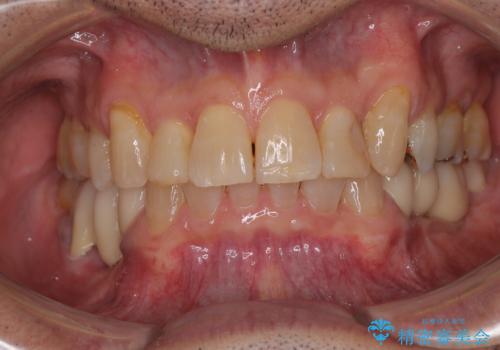

前歯の審美歯科治療 下顎の部分矯正と上顎前歯のオールセラミッククラウン